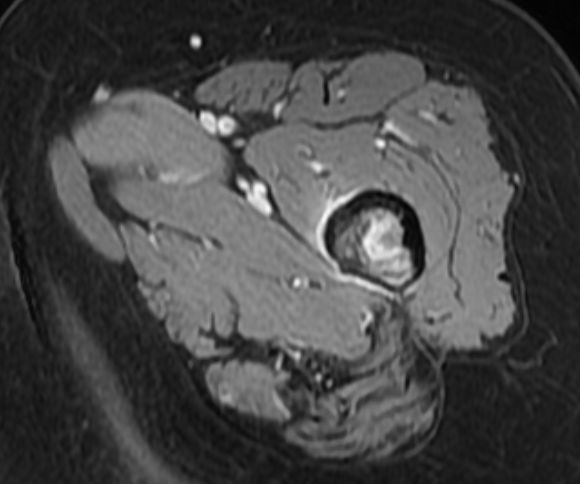

Femur | 58-jährige Frau mit Mammakarzinom links vor 14 Jahren und Mammakarzinom rechts vor 2 Jahren. Seit 4 Monaten Schmerzen im linken Oberschenkel. Jetzt Lungenmetastasen, osteoplastische Metastasen im LWk1 bis LWK4 sowie eine Osteolyse im linken Femur. | ||||||||||

MRT T2 KM Fett - saturiert![]() |

MRT T2 KM Fett - saturiert![]() | ||||||||||